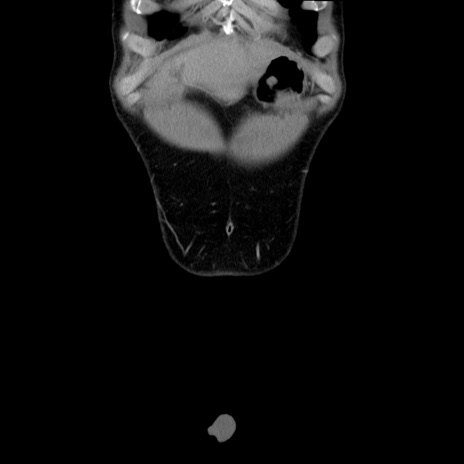

症例36(冠状断像)

【症例】20歳代 男性

【主訴】心窩部痛

【現病歴】今朝より上腹部痛あり。一旦軽快していたが再度出現したため救急要請。昨日夕に白身の魚を含む刺身を食べた。

【身体所見】BP 136/89mmHg、HR 74/min、BT 37.0℃、腹部:膨満、軟、心窩部に圧痛あり。反跳痛なし、筋性防御なし、腸雑音やや亢進あり。

【データ】WBC 17700、CRP 0.48